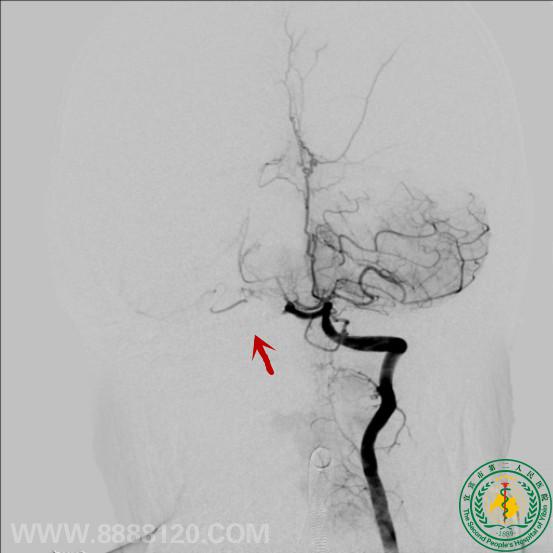

头颅CTA示右侧小脑前下动脉动脉瘤,DSA证实。

采用弹簧圈填塞、注胶技术治疗后,显示动脉瘤无显影。